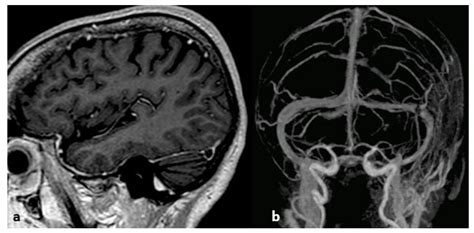

MRV is a non-invasive imaging technique that uses magnetic resonance imaging (MRI) to visualize the venous sinuses. It provides detailed images of the SSSV and can detect abnormalities such as thrombosis, aneurysms, or tumors. MRV is particularly useful in patients with suspected CVST, as it can provide information about the patency of the venous sinuses and the presence of any blood clots.

Diagnosis of CVST typically involves imaging studies, such as magnetic resonance venography (MRV) or computed tomography venography (CTV). Treatment may include anticoagulation therapy, thrombolysis, or surgical intervention.